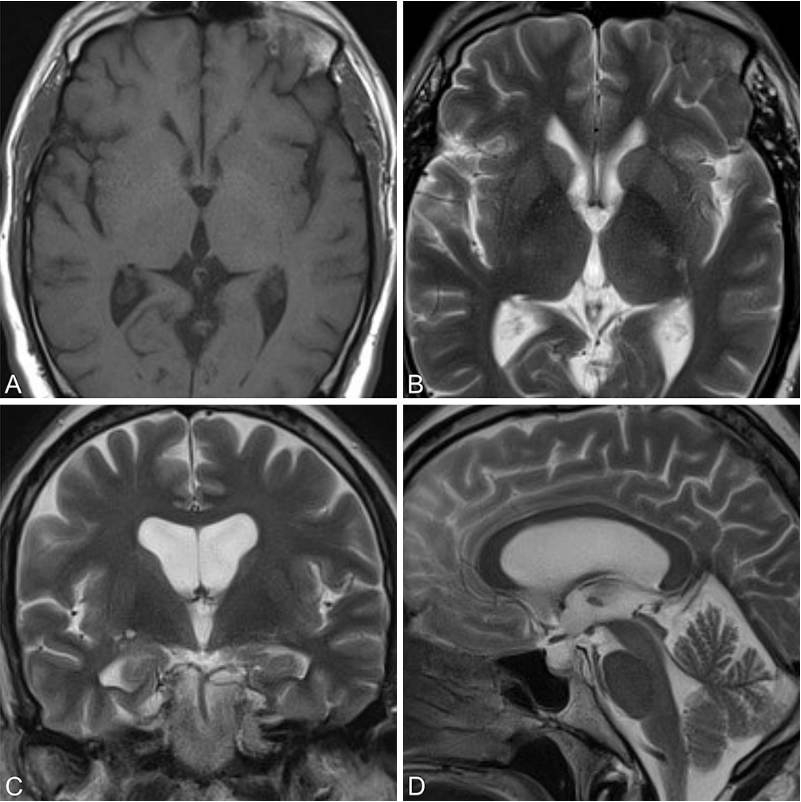

术后3年复查MRI(T1加权轴位A,T2加权轴位B、冠状位C、矢状位D)显示囊肿全切,无残留与复发征象,脑室系统形态恢复良好。